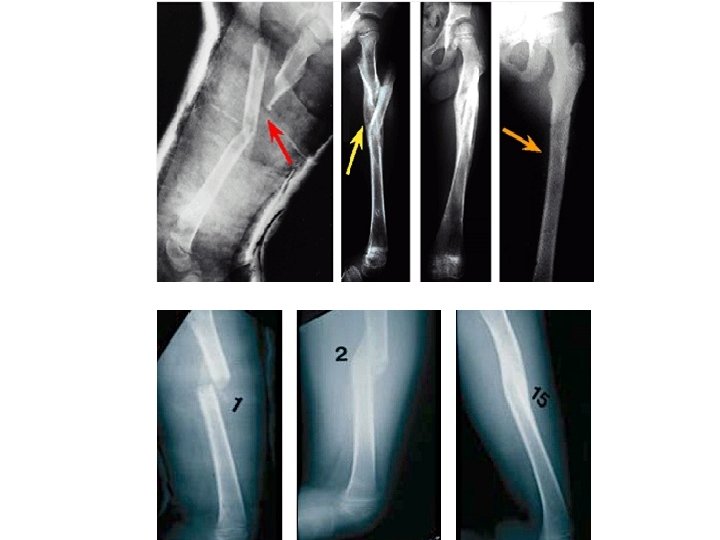

Femoral Shaft Fractures

Femoral Shaft # • 1. 6% of all pediatric # • M>F • Age: – (2 – 4) years old – Mid-adolescence • Adolescence >90% due to RTA

Femoral Shaft #- Mechanism of Injury • Direct trauma: – RTA, – Fall, or – Child abuse • Indirect trauma: – Rotational injury • Pathologic #: – Osteogenesis imperfecta, – Nonossifying fibroma, – Bone cysts, and – Tumors

Femoral Shaft #- Clinical Evaluation • Look: – – – Pain, Swelling of the thigh, Inability to ambulate, and Variable gross deformity Careful O/E of the overlying soft tissues to rule out the possibility of an open fracture (puncture wound) • Feel: – Tender # site • Careful neurovascular examination is essential

Femoral Shaft #- Radiology • AP and lateral views • Must include hip, knee joints

Femoral Shaft #- Classification Descriptive Anatomic • Open or closed • Level of fracture: • • (proximal, middle, distal) ⅓ • Fracture pattern: transverse, oblique, spiral, butterfly fragment, comminution • Displacement • Angulation Neck Subtrochanteric Shaft Supracondylar

Femoral Shaft #- Treatment Less than 6 m: • Pavlik Harness, • Traction then hip spica casting

Femoral Shaft #- Treatment 6 m – 6 y: • C. R and immediate hip spica casting (>95%) • Traction followed by hip spica casting (if there is difficulty to maintain length and acceptable alignment)

Femoral Shaft #- Treatment 6 – 12 y: • Flexible I. M. N • Bridge Plating • External Fixation

Femoral Shaft #- Treatment 6 – 12 y: • Flexible IMN • Bridge Plating • External Fixation

Femoral Shaft #- Treatment 6 – 12 y: • Flexible IMN • Bridge Plating • External Fixation: – Multiple injuries – Open fracture – Comminuted # – Unstable patient

Femoral Shaft #- Treatment 12 y to skeletal maturity: • Intramedullary fixation with either: – Flexible nails, or – Interlocked I. M nail

Femoral Shaft #- Complications • Malunion Remodeling will not correct rotational deformities • Nonunion (Rare) • Muscle weakness • Leg length discrepancy Secondary to shortening or overgrowth Overgrowth of 1. 5 to 2. 0 cm is common in 2 -10 year of age • Osteonecrosis with antegrade IMN <16 year